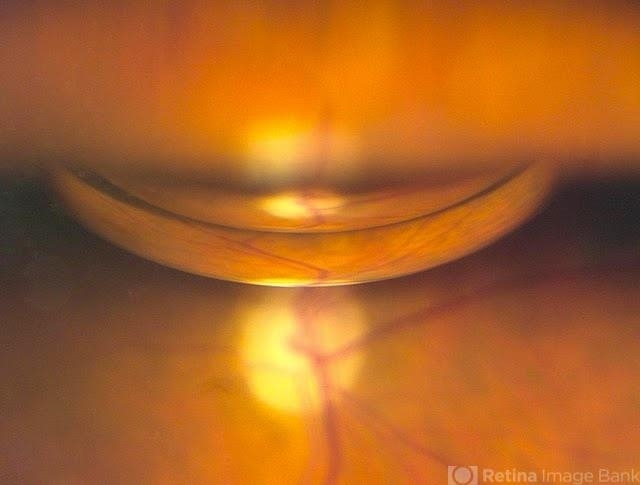

- Gas Bubble

- pneumatic retinopexy

- Patient had a pneumatic retinopexy for retinal detachment. Fundus shows C3F8 gas bubble superiorly.